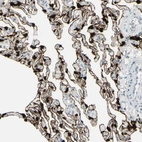

Immunohistochemistry analysis in human lung and lymph node tissues using HPA011888 antibody. Corresponding C1orf116 RNA-seq data are presented for the same tissues.